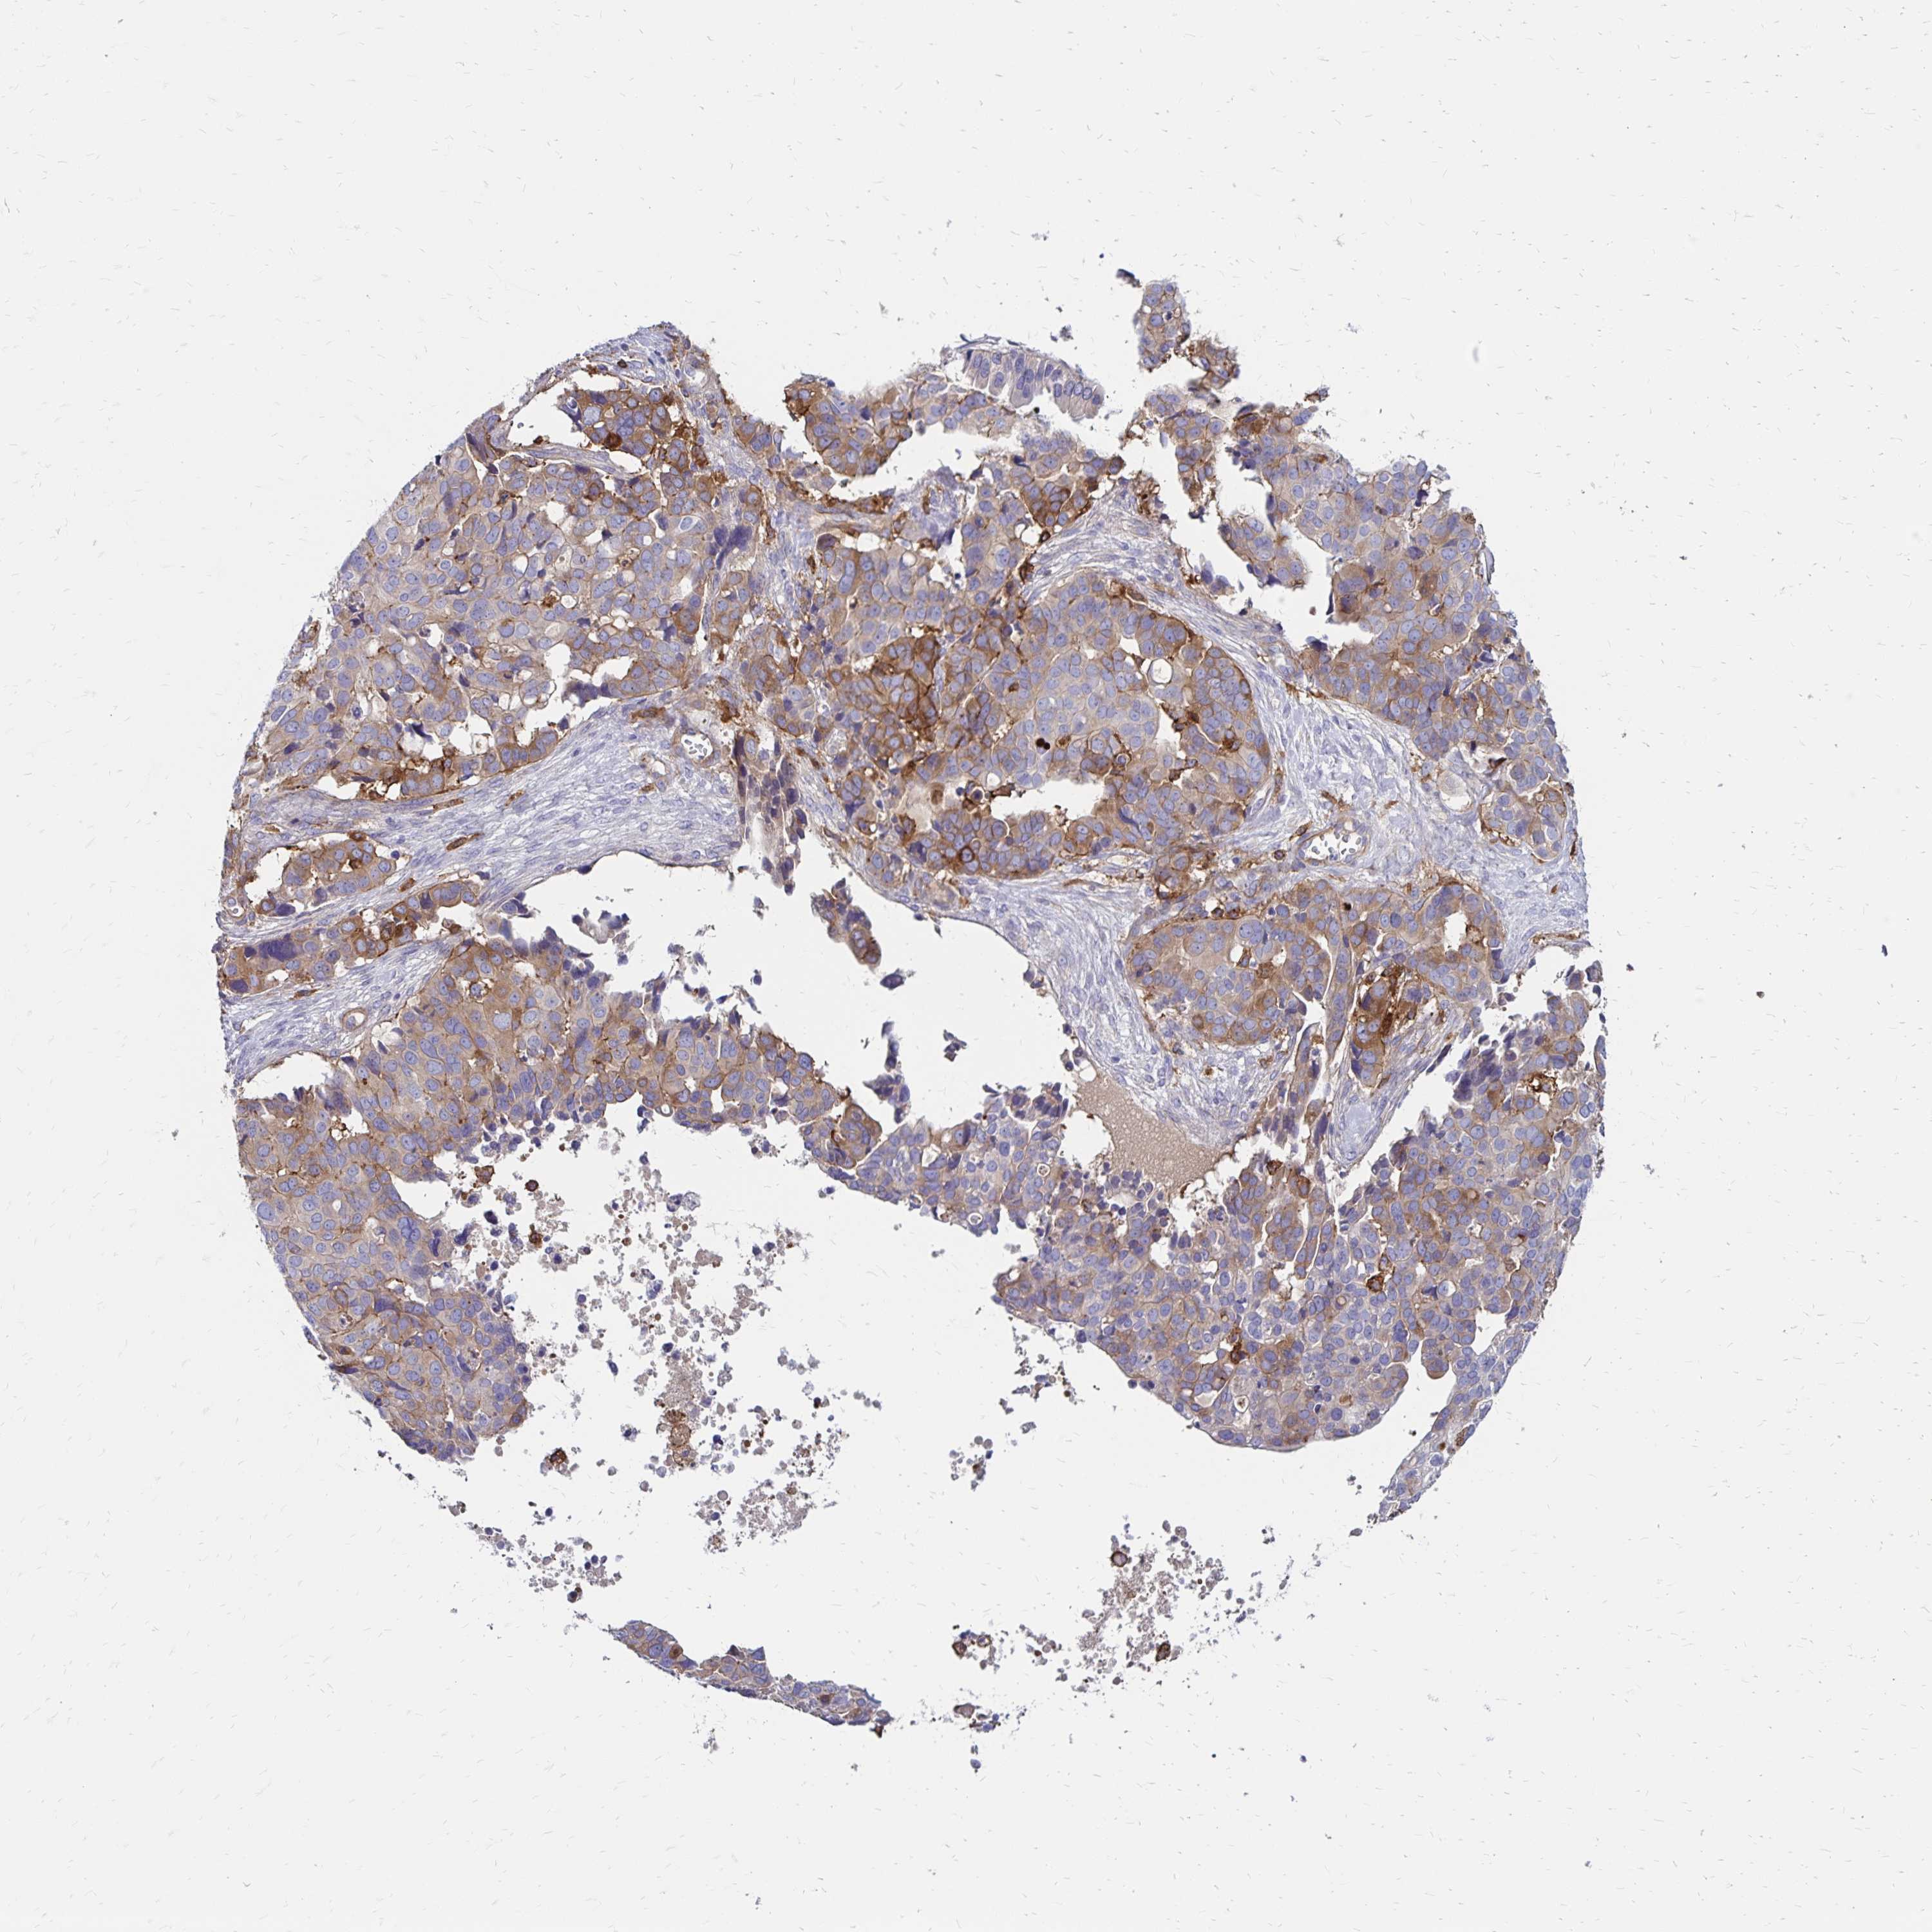

OVARIAN CANCER - Protein expressioni

A mouse-over function shows sample information and annotation data. Click on an image to view it in a full screen mode. Samples can be filtered based on level of antibody staining by selecting one or several of the following categories: high, medium, low and not detected. The assay and annotation is described here.

Note that samples used for immunohistochemistry by the Human Protein Atlas do not correspond to samples in the TCGA dataset.

Antibody stainingi

Antibody staining in the annotated cell types in the current human tissue is reported as not detected, low, medium, or high, based on conventional immunohistochemistry profiling in selected tissues. This score is based on the combination of the staining intensity and fraction of stained cells.

Each image is clickable and will lead to virtual microscopy that enables deeper exploration of all samples and also displays staining intensity scores, fraction scores and subcellular localization as well as patient and tissue information for each sample.

Antibody HPA055338

Antibody HPA056015

Staining

High

Medium

Low

Not detected

Intensity

Strong

Moderate

Weak

Negative

Quantity

>75%

75%-25%

<25%

None

Location

Nuclear

Cytoplasmic/membranous

Cytoplasmic/membranous,nuclear

Cystadenocarcinoma, serous, NOS

Cystadenocarcinoma, mucinous, NOS

Carcinoma, endometroid